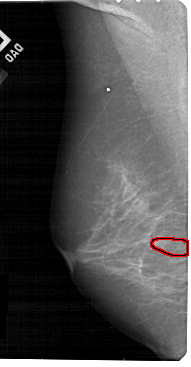

FILE: A_1839_1.LEFT_CC.OVERLAY

TOTAL_ABNORMALITIES 1

ABNORMALITY 1

LESION_TYPE CALCIFICATION TYPE PLEOMORPHIC DISTRIBUTION CLUSTERED

ASSESSMENT 4

SUBTLETY 3

PATHOLOGY BENIGN

TOTAL_OUTLINES 1

BOUNDARY